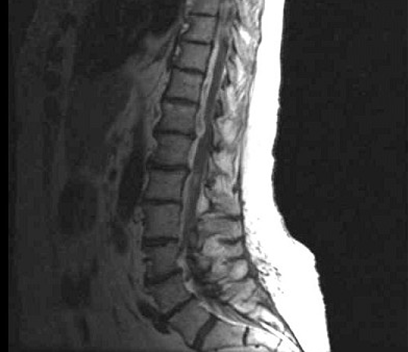

女,34岁,发热,腰部局限性疼痛、活动受限半月余,查体有压痛、叩痛,MRI检查如图,最可能的诊断为()

男,32岁,低热、乏力,背痛,活动受限,结合CT检查选择最可能的诊断()

A.化脓性脊柱炎